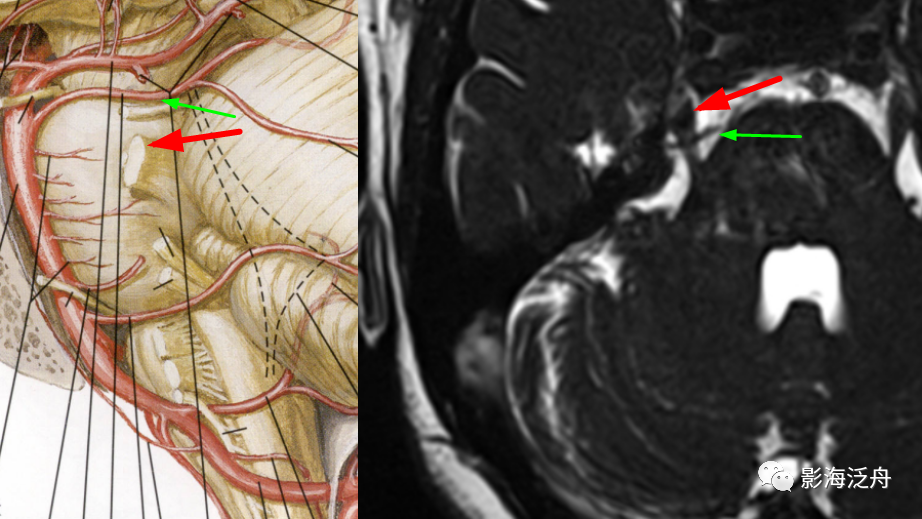

在MRA图上观察一下这三支动脉。如图所示,红箭:小脑上动脉;绿箭:右侧小脑下前动脉;小脑下后动脉未在图中显示(MRA中小脑下后动脉很少能显示出来)。

在轴位MR图像上观察并准确辨识出相应的神经和血管,常规的FSE T2WI也可以看到这些颅神经和血管,但不够清晰,尽量还是在更专业的3D重T2WI序列或3D B_FFE序列上观察,如下图↓